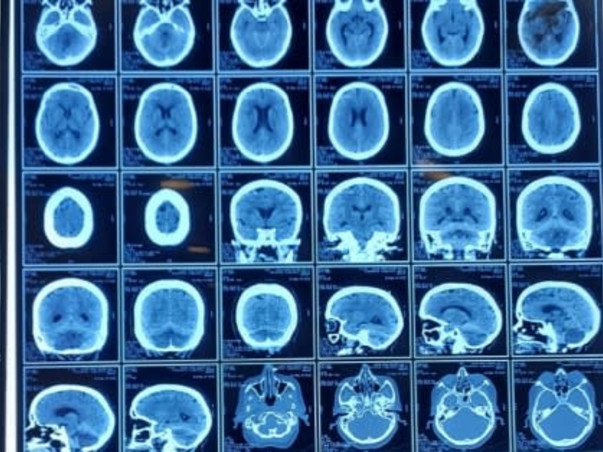

My mother has suffered a Brain Stroke. She is currently admitted and receiving medication & treatment at Apex Super Speciality Hospital, Varanasi. She has undergone one surgery till now.

She need to go through another major operation to remove blood clotting from the brain. Hence in the next few days, we need Rs.5,00,000 more for further treatment. Please come forward to support my cause. Any contribution will be of immense help. Do contribute and share this crowdfunding fundraiser link with your friend's and family.